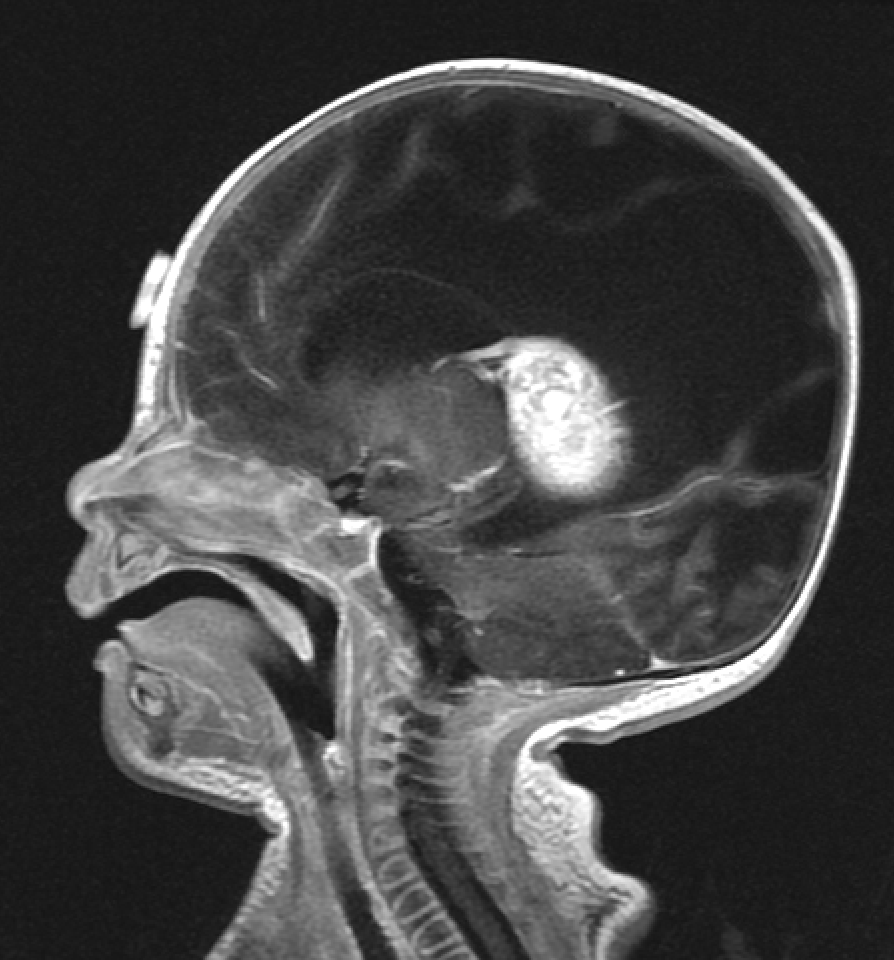

A sagittal MRI scan of a paediatric brain revealing a large, bright (enhancing) mass in the posterior region, typical of a brain tumour requiring neurosurgical consultation.